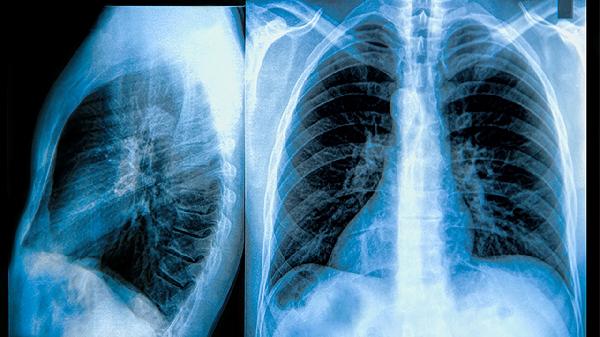

由于慢阻肺是进行性加重的器质性疾病,中医无法逆转肺功能损伤。急性加重期需及时使用西医支气管扩张剂和抗感染治疗,单纯中医干预可能延误病情。重度肺气肿或呼吸衰竭患者更需要氧疗、无创通气等西医支持手段。中药与西药联用时可能存在相互作用风险,如茶碱类与部分清热药同服易引发中毒。